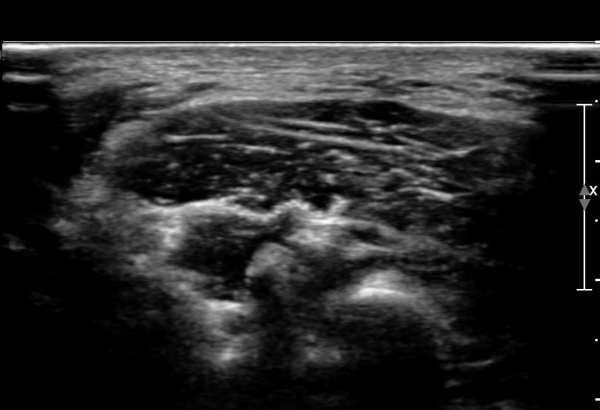

ÃÊÀ½ÆÄ ¼Ò°ß : ¸ñ ¿ÜÃø Á߾ӺΠȾ´Ü¸é°Ë»ç»ó Èä¼âÀ¯µ¹±Ù ÈÄ¹Ý °ß°©°Å±Ù Ç¥Ãþ¿¡¼­ ôÃߺνŰæÀÌ Àú¿¡ÄÚ

¿øÇü ±¸Á¶¹°·Î °üÂûµÈ´Ù(»çÁø 1, 2, 3).